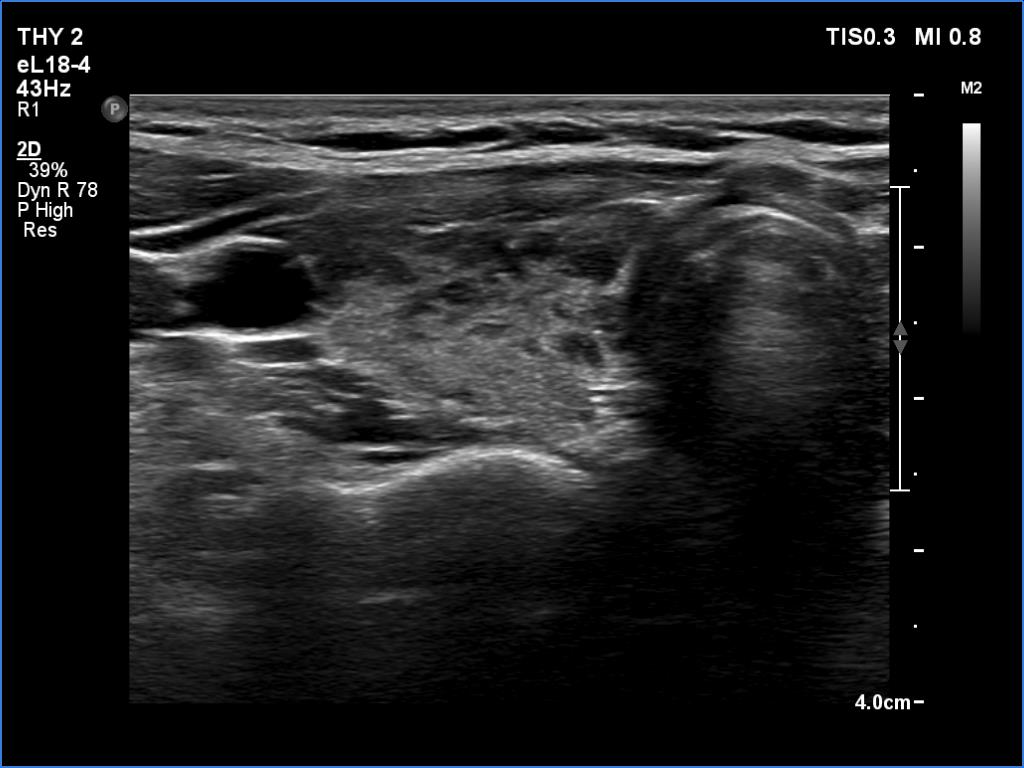

A patient operated on Graves' disease then received radioiodine therapy - case 321

After the surgery before the radioiodine treatment

After the radioiodine treatment

The patient had a recurrent hyperthyroidism 15 years after a bilateral subtotal resection performed because of relapsing Graves disease. Several months after the first visit, the patient underwent on radioiodine treatment. The right images were recorded 5 years after the isotope therapy.

In surgically treated thyroids, the histopathological findings must be taken ito account in order to avoid mispretating discrete lesions. If the previous histopathology did not find nodule than an ambiguous lesion is very rarely a true nodule.

The echonormal areas which surround the hypoechoic lesion can be tracked up, down and sideways, therefore these do not correspond to thyroid tissue but to connective tissue.